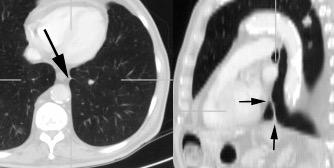

Consolidación por Infarto pulmonar. (TEP)

Diafragma “colgante” (“dangling sign”)

(“Dangling sign”)

TC. Mejor con multicorte. (reconstrucciones).

Asociación: Aire en pared.

Fracturas costal .Rotura esplénica. Neumoperitoneo.

Diafragma discontinúo Herniación de la grasa omental

Desser TS et al.The dangling diaphragm sign: sensitivity and comparison with existing CT signs of blunt traumatic diaphragmatic rupture. Emerg Radiol 2010